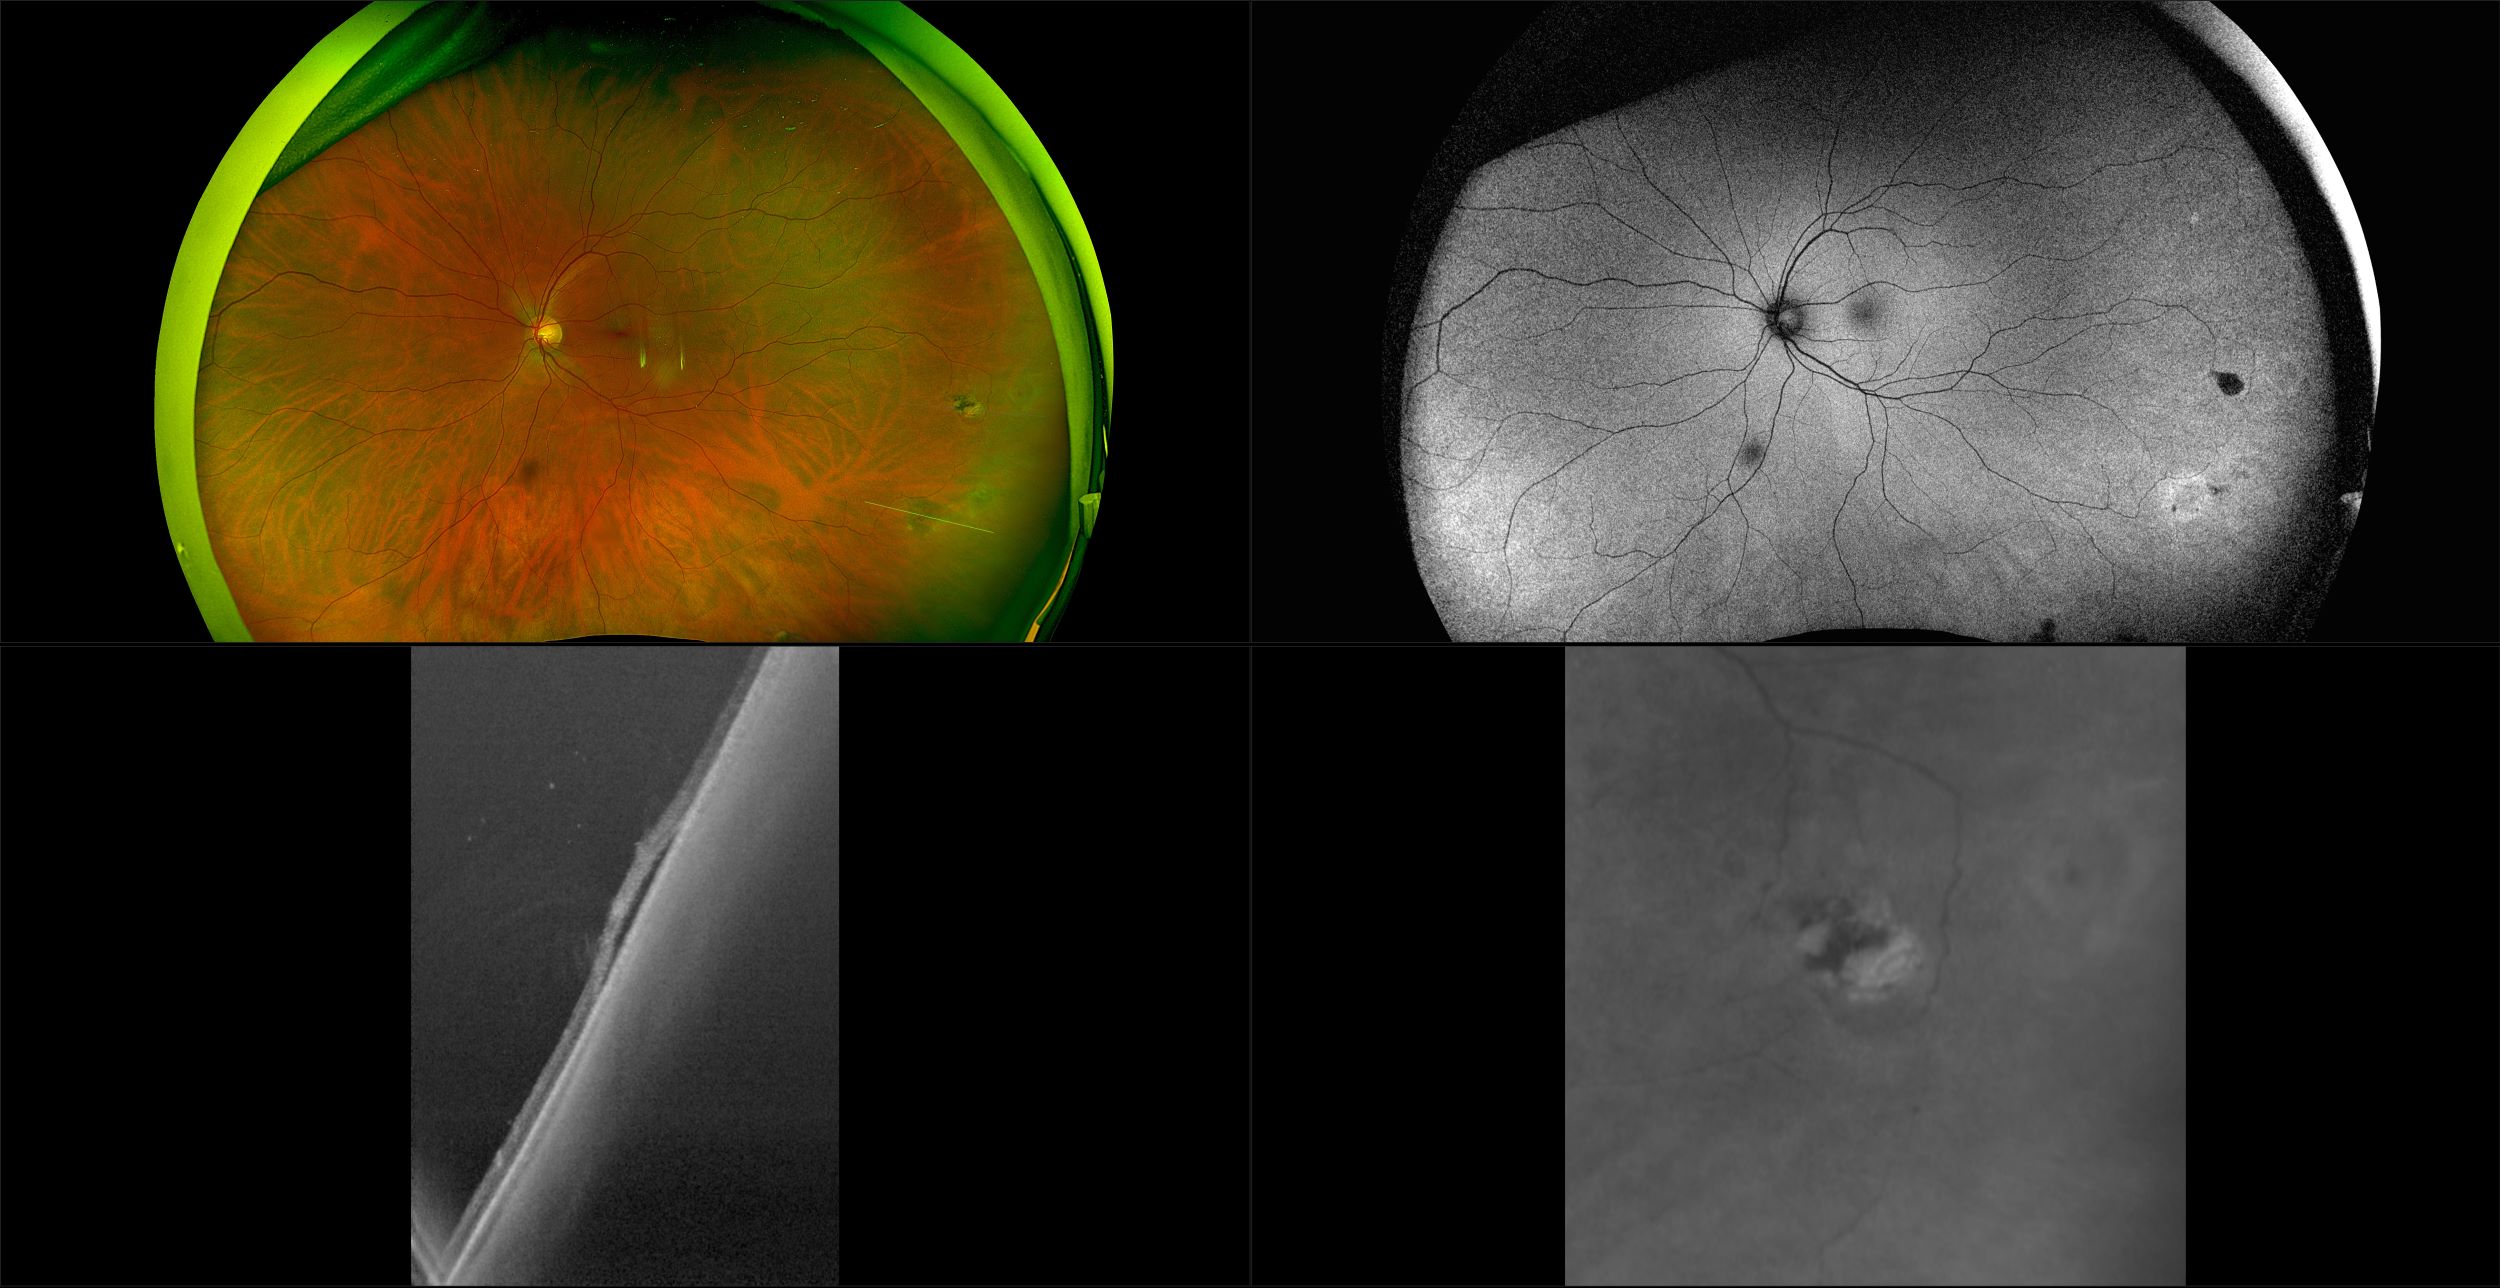

California - AMD, RG, AF

Age-related macular degeneration is found in two forms 1. Dry early form. 2. Wet (serous leakage or whole blood). Early dry form typically has drusen (usually around 63u) and RPE degeneration and only needs periodic follow-ups, intermediate dry form has large drusen (>125u) and RPE degeneration and proliferation which requires examinations every 3 to 6 months depending on the severity of the presentation.